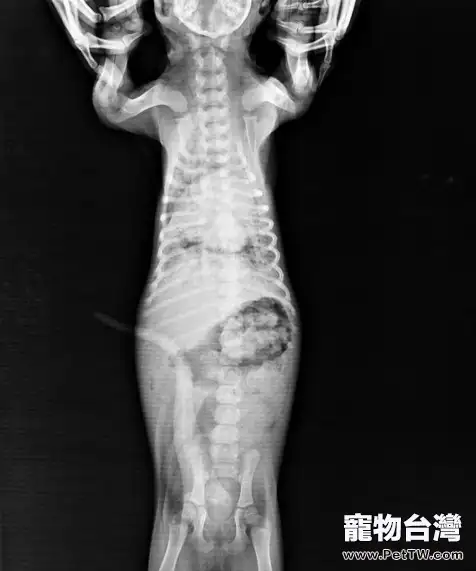

傳染病排查未見異常。白血球(WBC)急劇升高,其中嗜中性白細胞大量增加,且有大量核左移現象。X射線檢查右側肺葉有大片陰影區域。

X射線檢查

根據臨床檢查的特徵:高熱,鐵銹色鼻液,結合聽診以及實驗室白細胞檢查和X射線檢查結果,確診為大葉性肺炎。